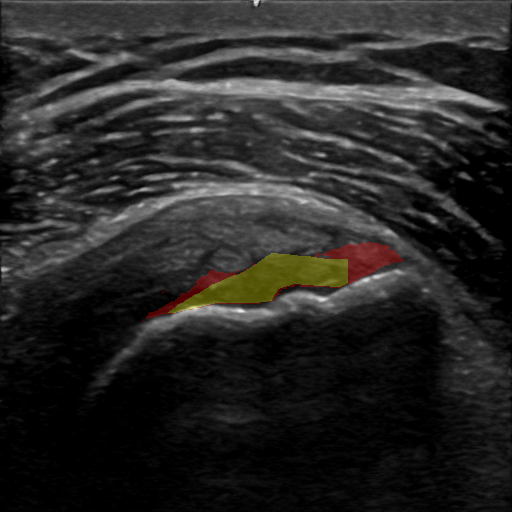

To reduce the probability of selecting false positive points, a threshold is applied to the coarse pathology segmentation masks before selection. We denote the selected positive points as ptspos={ptsipos}i=1k𝑝𝑡superscript𝑠𝑝𝑜𝑠superscriptsubscript𝑝𝑡subscriptsuperscript𝑠𝑝𝑜𝑠𝑖𝑖1𝑘pts^{pos}=\{pts^{pos}_{i}\}_{i=1}^{k}italic_p italic_t italic_s start_POSTSUPERSCRIPT italic_p italic_o italic_s end_POSTSUPERSCRIPT = { italic_p italic_t italic_s start_POSTSUPERSCRIPT italic_p italic_o italic_s end_POSTSUPERSCRIPT start_POSTSUBSCRIPT italic_i end_POSTSUBSCRIPT } start_POSTSUBSCRIPT italic_i = 1 end_POSTSUBSCRIPT start_POSTSUPERSCRIPT italic_k end_POSTSUPERSCRIPT. This process is illustrated in Fig. 2.

Refer to caption

Figure 2: An illustration of our positive (foreground) points selection module, depicted in red. A threshold is applied to the coarse segmentation prediction. A k𝑘kitalic_k- medoids clustering algorithm is applied to select k𝑘kitalic_k positive pathology points.